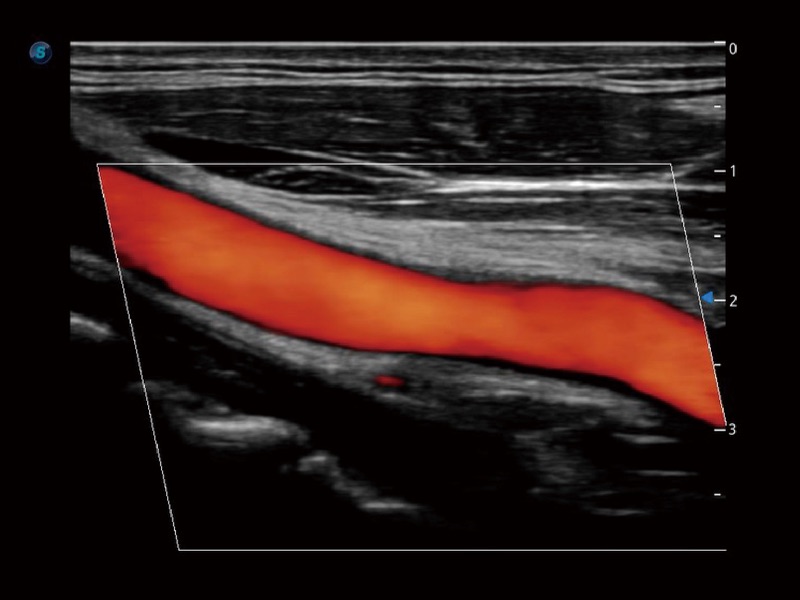

高分辨率血流成像技術(shù)提高了對(duì)低速血流信號(hào)的檢測(cè)能力。在提高空間分辨率的同時(shí),也克服了血流外溢現(xiàn)象,為用戶(hù)提供更加真實(shí)的血流動(dòng)力學(xué)信息。

心血管應(yīng)用